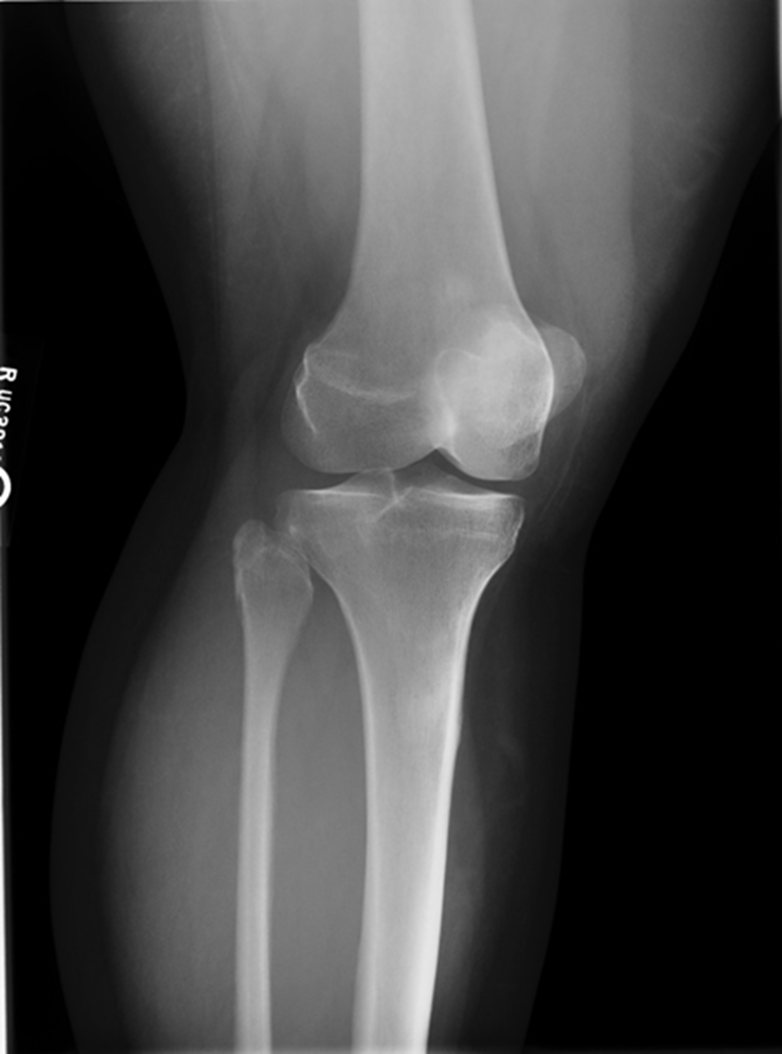

Trauma and Non Trauma AP Knee

•Evidence of proper collimation and the presence of a side marker placed clear of the anatomy of interest

•Knee fully extended if patient’s condition permits

•Entire knee without rotation

•Femoral condyles symmetric and tibia intercondylar eminence centered

•Slight superimposition of the fibular head if the tibia is normal

•Patella completely superimposed on the femur

•Open femorotibial joint space, with interspaces of equal width on both sides if the knee is normal

•Bony trabecular detail and surrounding soft tissues

Non Trauma PA Erect (RH)

(patient age 40 and older)

•Both knees without rotation (RH only does the side of interest)

•Knee joint spaces centered to the exposure area (RH only does the side of interest)

Bony trabecular detail and surrounding soft tissue

Repeat for not enough exposure -3.6

Increase Density by 2

Fix centering

joint space is narrowed off, condyles look symmetric

platues look equal

slight superimposition of tibia/fibula

GOOD IMAGE repeat for exposure index